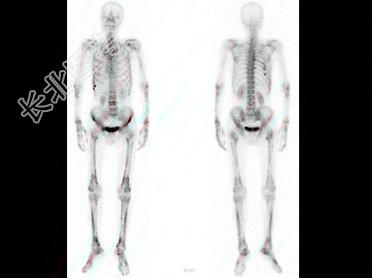

- 多项选择题男,67岁, 诉全身多处疼痛4月余,行全身骨显像如图。对此影像的描述下列正确的有 ( )

A、有严重的骨质疏松

B、正常的骨影像

C、有双轨征

D、提示原发病可能为肺癌

E、提示患者有慢性肺部疾患